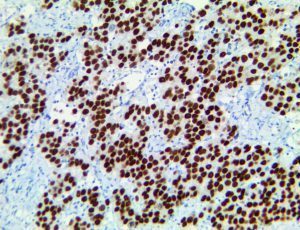

It is the ICU physician who is most likely to witness one of the deadliest manifestations of the abnormal immunological response, the cytokine storm syndrome (CSS). This response is also referred to by some as the cytokine release syndrome (CRS). CSS is characterized by continuous activation and expansion of macrophage and lymphocyte populations, which secrete large amounts of cytokines, causing the cytokine storm. This massive cytokine release is akin to hemophagocytic lymphohistiocytosis (HLH) disease, a syndrome characterized by initial unchecked and persistent activation of cytotoxic T lymphocytes and NK cells.

Clinical and laboratory manifestations of HLH include fever, enlarged liver and/or spleen, neurologic dysfunction, coagulopathy, liver dysfunction, cytopenias (i.e., low levels of erythrocytes, leukocytes, and/or platelets), hypertriglyceridemia, hyperferritinemia, hemophagocytosis, and eventually diminished NK cell activity as the immune system becomes progressively paralyzed. HLH can be familial (primary HLH) or secondary to another disease process (sHLH), such as rheumatic disease, in which it is referred to as macrophage activation syndrome (MAS, characterized by elevated ferritin).